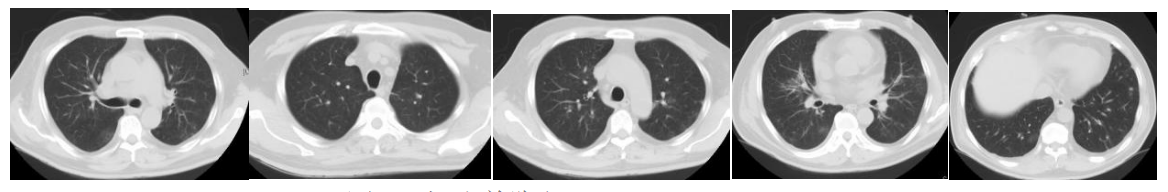

8月14日,复查影像学检查(依拉环素治疗14天),胸部CT:双肺感染较前吸收好转,双侧胸腔积液较前减少;头颅CT:右侧大脑半球低密度影范围较前增大,考虑脑梗塞并右侧颞叶出血可能,上颌窦炎,真菌感染可能。

图15. 胸部CT(2023-08-14)

图16. 头颅CT(2023-08-14)